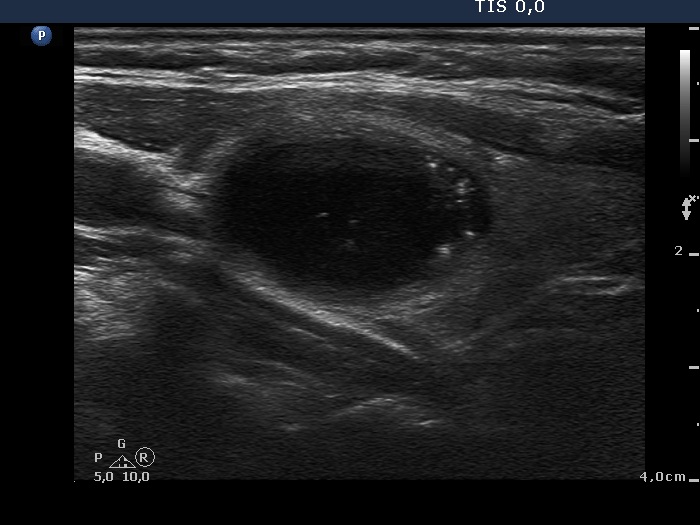

Intranodular hyperechogenic figures - case 443 (ultrasonographic picture 9)

Left lobe, another longitudinal view.